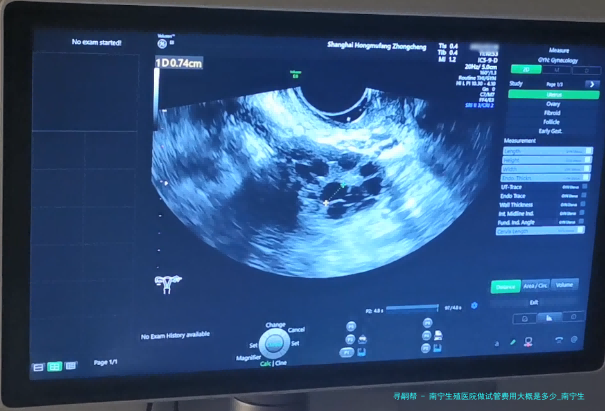

下方是南宁生殖医院区分试管项目的详细费用参考表。

| 项目 | 费用(元) |

|---|---|

| 基本治疗费 | 5000-10000 |

| 辅助检查和药品费 | 3000-5000 |

| 手术器械使用费 | 2000-3000 |

| 麻醉师操作费 | 500-1000 |

请关注,之上费用仅作参考,具体费用于南宁生殖医院实际收费为准。